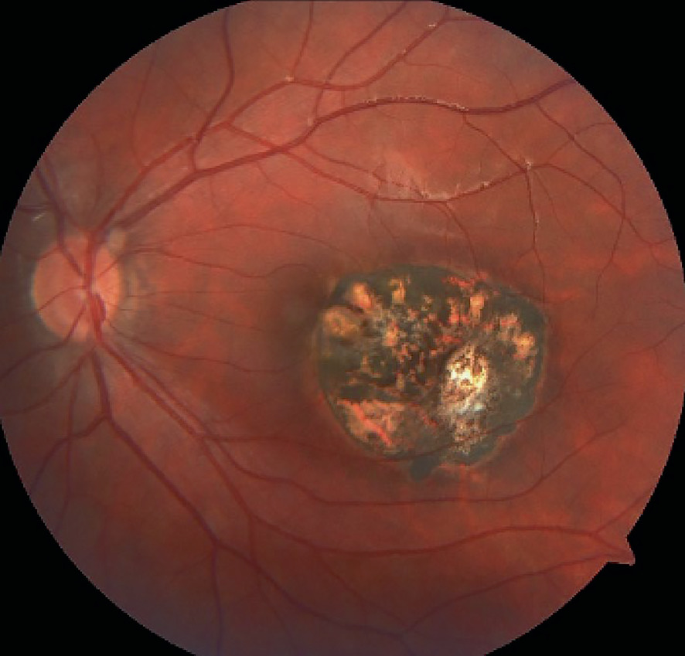

Toxoplasmosis Gondii Chorioretinitis

Toxoplasmic chorioretinitis - Wikipedia A typical chorioretinitis by toxoplasma Ocular Toxoplasmosis: Overview, Pathogenesis, Congenital Versus ... Toxoplasmosis - EyeWiki Fundus photograph of left eye showing active chorioretinitis of ... Toxoplasmosis Gondii Chorioretinitis